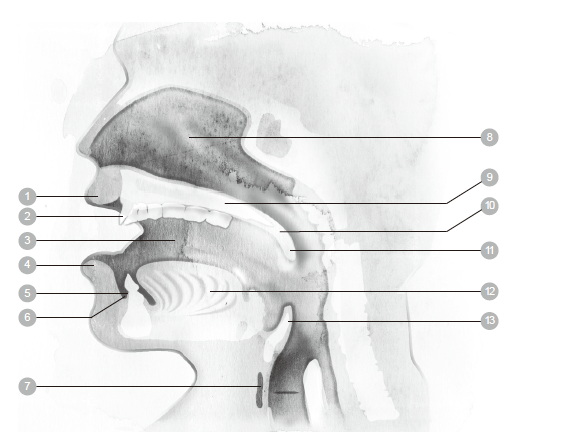

1 上龈 7 甲状软骨 13 扁桃腺

2 牙齿 8 喉头 14 咽头

3 嘴唇 9 鼻腔 15 会厌(喉头盖)

4 舌头 10 硬腭 16食道

5 下颌 11 软腭 17 声带

6 舌骨 12 悬雍垂(小舌)

1 鼻腔 3 腭咽腔

2 口腔 4 咽腔

1 上唇 5 牙床 9 硬腭 13 会厌(喉头盖)

2 牙齿 6 前庭 10 软腭

3 脸颊 7 舌骨 11 悬雍垂(小舌)

4 下唇 8 鼻腔 12 舌头